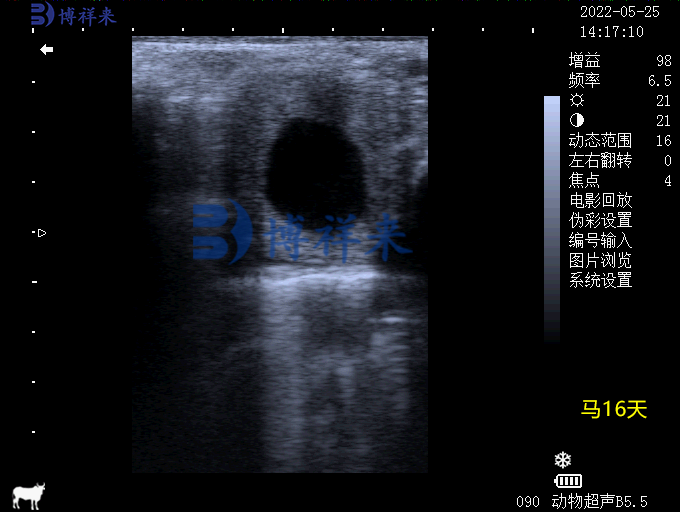

二、妊娠早期检测

传统手段通常在配种后40天才能确认母马是否妊娠,而使用马用B超机,在 14-16天 就能看到受精卵在子宫内的液性暗区。早期检测的优势包括: